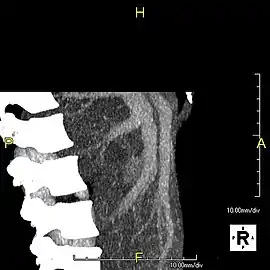

Axial CT image showing anomalous hepatic veins coursing on the liver's subcapsular anterior surface[70]

Maximum intensity projection (MIP) CT image as viewed anteriorly showing the anomalous hepatic veins coursing on the anterior surface of the liver

Lateral MIP view in the same patient as previous image

With the recent advances of noninvasive imaging, living liver donors usually have to undergo imaging examinations for liver anatomy to decide if the anatomy is feasible for donation. The evaluation is usually performed by multidetector row computed tomography (MDCT) and magnetic resonance imaging (MRI). MDCT is good in vascular anatomy and volumetry. MRI is used for biliary tree anatomy. Donors with very unusual vascular anatomy, which makes them unsuitable for donation, could be screened out to avoid unnecessary operations.

MDCT image. Arterial anatomy contraindicated for liver donation

MDCT image. Portal venous anatomy contraindicated for liver donation

MDCT image. 3D image created by MDCT can clearly visualize the liver, measure the liver volume, and plan the dissection plane to facilitate the liver transplantation procedure.

Phase contrast CT image. Contrast is perfusing the right liver but not the left due to a left portal vein thrombus.